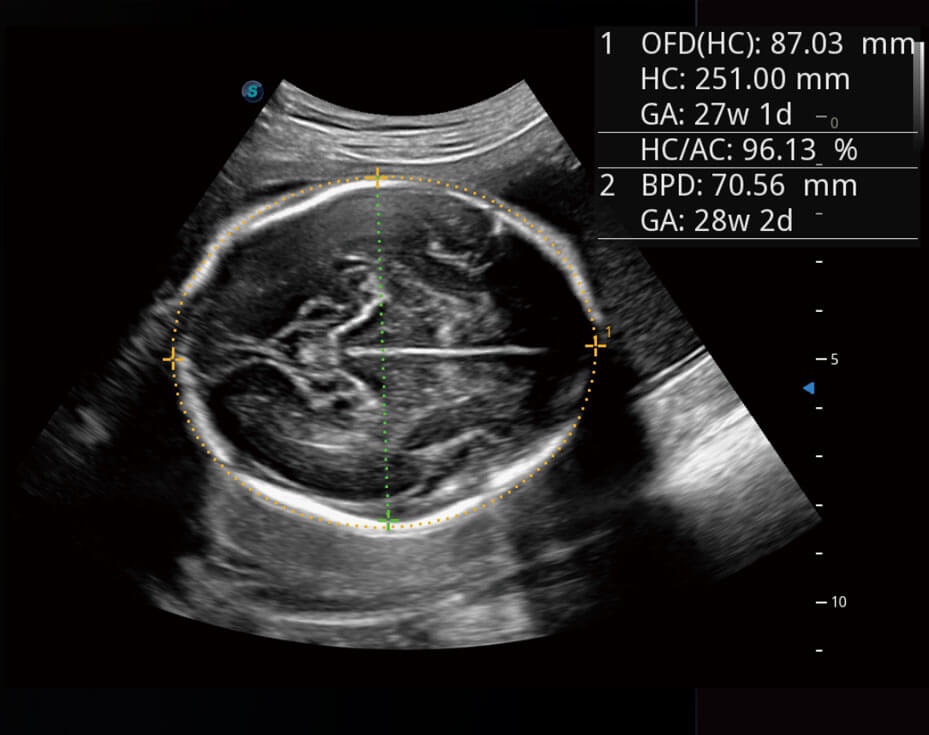

Tự động phát hiện và đo 16 thông số thai nhi bằng trí tuệ nhân tạo AI trong quy trình siêu âm sản khoa.

Tự động thu thập mặt phẳng tiêu chuẩn (có sẵn trên BPD/AC/HC/FL).

Sinh trắc học và báo cáo tự động.

Đã xác minh hơn 10000 trường hợp với độ chính xác 98%.

Auto OB

Tự động OB giúp siêu âm thai nhi nhanh chóng và hiệu quả. Kết quả nhất quán làm giảm sự thay đổi phụ thuộc vào người dùng.